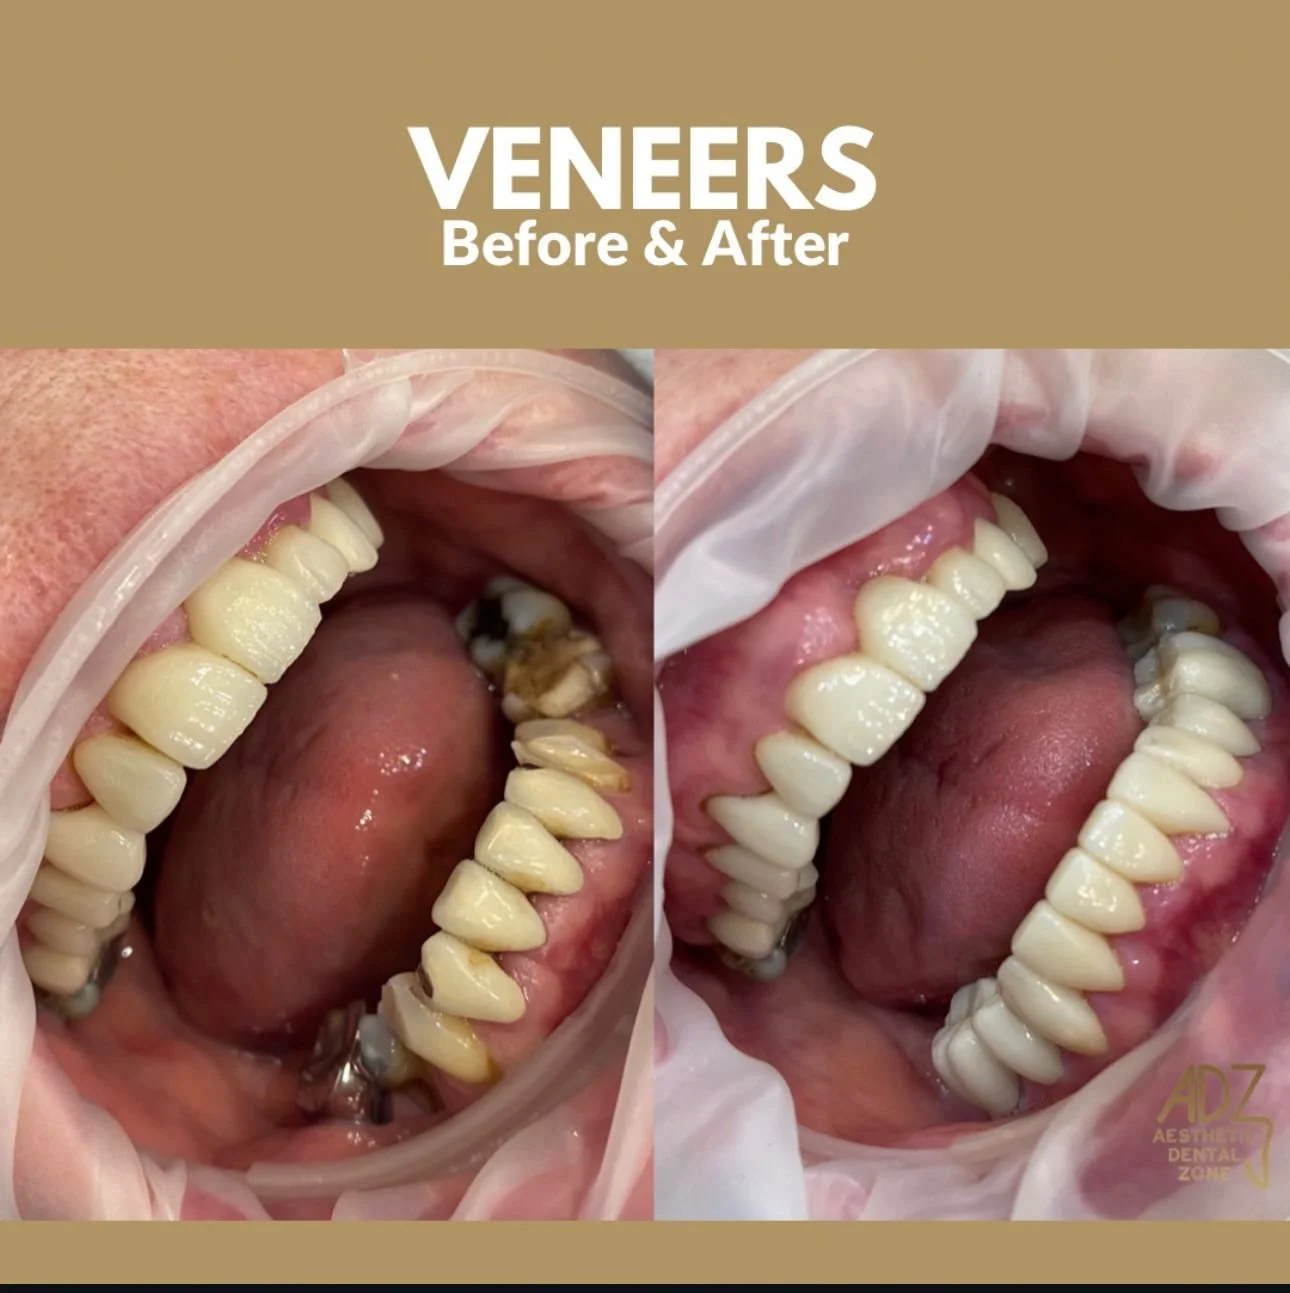

VENEERS

Ceramic Veneers are thin Porcelain facings that are bonded to the teeth to improve appearance. Porcelain laminate veneers (Ceramic veneers) can correct imperfections (chips, cracks, gaps, misalignments, and discolorations in the front teeth) to help you achieve a magnificent, durable, and long-lasting smile. In some cases, it can even protect the teeth from tear and wear. It is an attractive option for people who are not interested in orthodontic braces to straighten teeth. The whole procedure can be completed in 2 dental visits in one week and produce ultimate durable aesthetics. Ceramic Veneers are very thin, custom-made shells crafted of tooth-colored materials designed to cover the front side of the teeth. Veneers help people accomplish a healthy, natural-looking, and beautiful smile with little or no discomfort.